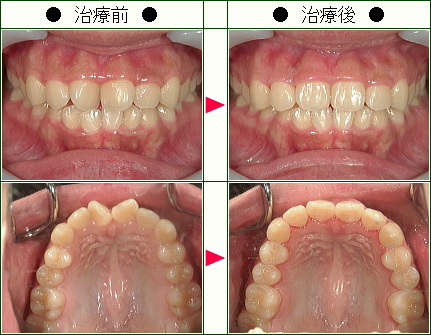

歯のデコボコ矯正の治療症例解説<上だけの症例>(19歳以下)--部分矯正--その4

☆歯のデコボコ矯正症例[松村様 15歳 女性]